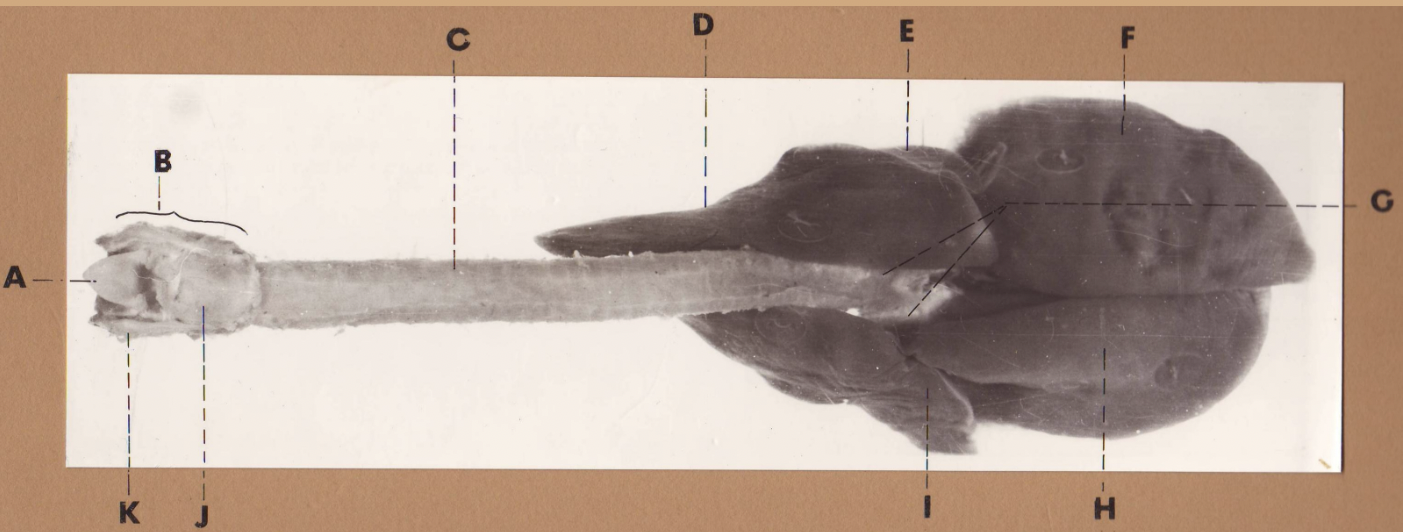

A

(cat larynx/trachea/lungs, dorsal)

epiglottis

B

(cat larynx/trachea/lungs, dorsal)

larynx

C

(cat larynx/trachea/lungs, dorsal)

trachea

D

(cat larynx/trachea/lungs, dorsal)

R cranial lobe

E

(cat larynx/trachea/lungs, dorsal)

middle lobe

F

(cat larynx/trachea/lungs, dorsal)

R caudal lobe

G

(cat larynx/trachea/lungs, dorsal)

primary bronchi

H

(cat larynx/trachea/lungs, dorsal)

L caudal lobe

I

(cat larynx/trachea/lungs, dorsal)

L cranial lobe

J

(cat larynx/trachea/lungs, dorsal)

cricoarytenoideus dorsalis m

K

(cat larynx/trachea/lungs, dorsal)

thyroid

A

(cat larynx/trachea/lungs, dorsal)

epiglottis

B

(cat larynx/trachea/lungs, dorsal)

larynx

C

(cat larynx/trachea/lungs, dorsal)

trachea

D

(cat larynx/trachea/lungs, dorsal)

R cranial lobe

E

(cat larynx/trachea/lungs, dorsal)

middle lobe

F

(cat larynx/trachea/lungs, dorsal)

R caudal lobe

G

(cat larynx/trachea/lungs, dorsal)

primary bronchi

H

(cat larynx/trachea/lungs, dorsal)

L caudal lobe

I

(cat larynx/trachea/lungs, dorsal)

L cranial lobe

J

(cat larynx/trachea/lungs, dorsal)

cricoarytenoideus dorsalis m

K

(cat larynx/trachea/lungs, dorsal)

thyroid